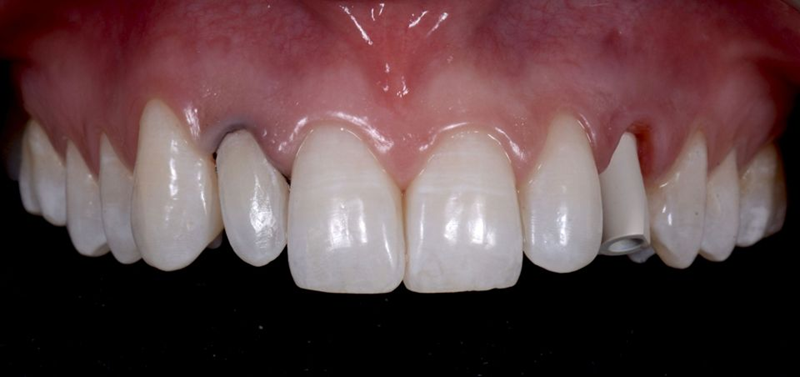

患者和我们的团队对最终结果在健康、美观和功能方面都非常满意。即使详细分析,也很难识别出最终的修复体(图63)。

Fig. 63: Frontal view of the final result.

在这一点上,我们可以说我们满足了患者的所有需求和期望,并且与基线情况相比(图 64),我们可以看到一个很大的改进。

Fig. 64: Before and after the treatment: Note how the smile of the patient was improved simply by...

新的笑容和谐地融入了患者的脸上(图65-66),最后,她参与了每年一次随访的维护计划。